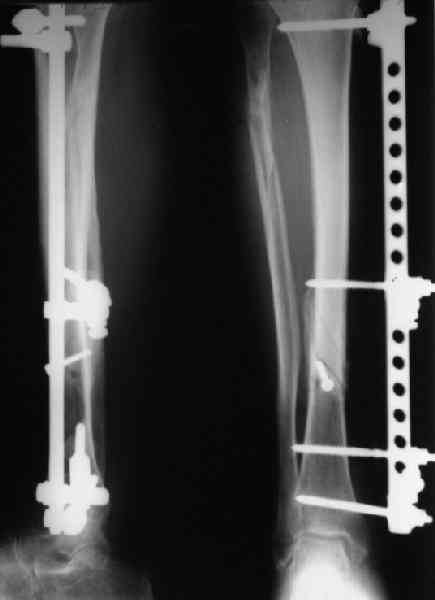

Вроде как раз удалось суммировать достоинства обоих методов, и минимизировать их недостатки. Аппарат - минимальный, то есть время/силы сэкономили, мышцы сильно не прошили, проблем с разработкой не будет, нагружать можно, при необходимости можно напрячь на дистракцию или компрессию. Внутренняя фиксация - и малоинвазивная (особенно если закрыто делать), и недорого, и нет массивных имплантатов, отслойки тканей. Если не срастется, в отличие от несращения на пластине, удалить один винт всего надо, и аппарат уже есть. В общем, дешево и сердито.

Этот подход как раз в русле модного в последние годы направления - закрытая репозиция, сочетание внешней и минимальной внутренней фиксации.

Поздравляю от всей души. Эта методика описана в последней монографии Вебера под логотипом MiniMax o\s, если я правильно помню. На самом деле очень перспективная технология сочетающая в себе основные два принципа остеосинтеза АО 1) межотломковая компрессия 2)шинирование (или шунтирование нагрузки - это по-моему) и + Российский принцип срочная компенсация опоросопобности, что позволяет аппарат Илизарова. Еще раз поздравляю от всей души ЛАФ.

Безусловно, в тех центрах, где доступны все существующие современные методы, этот просто не нужен. Можно закрыто заштифтовать, и все. Но для отделений с ограниченными возможностями, где до сих пор широко применяется открытый остеосинтез большеберцовой кости одним винтом с последующим наложением гипсовой повязки на 6-8 недель, этот вариант имеет преимущества - возможны ранние и функция, и нагрузка.